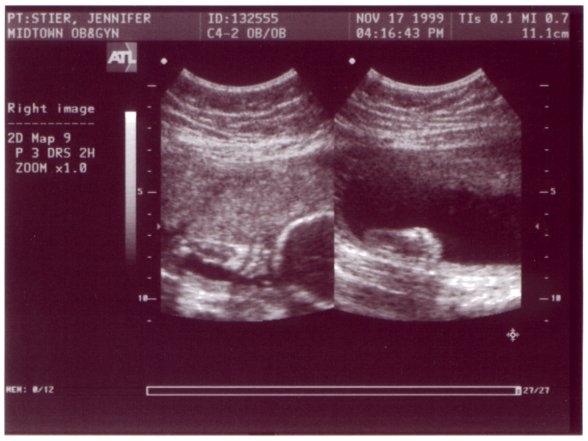

Ultrasound Picture No. 5